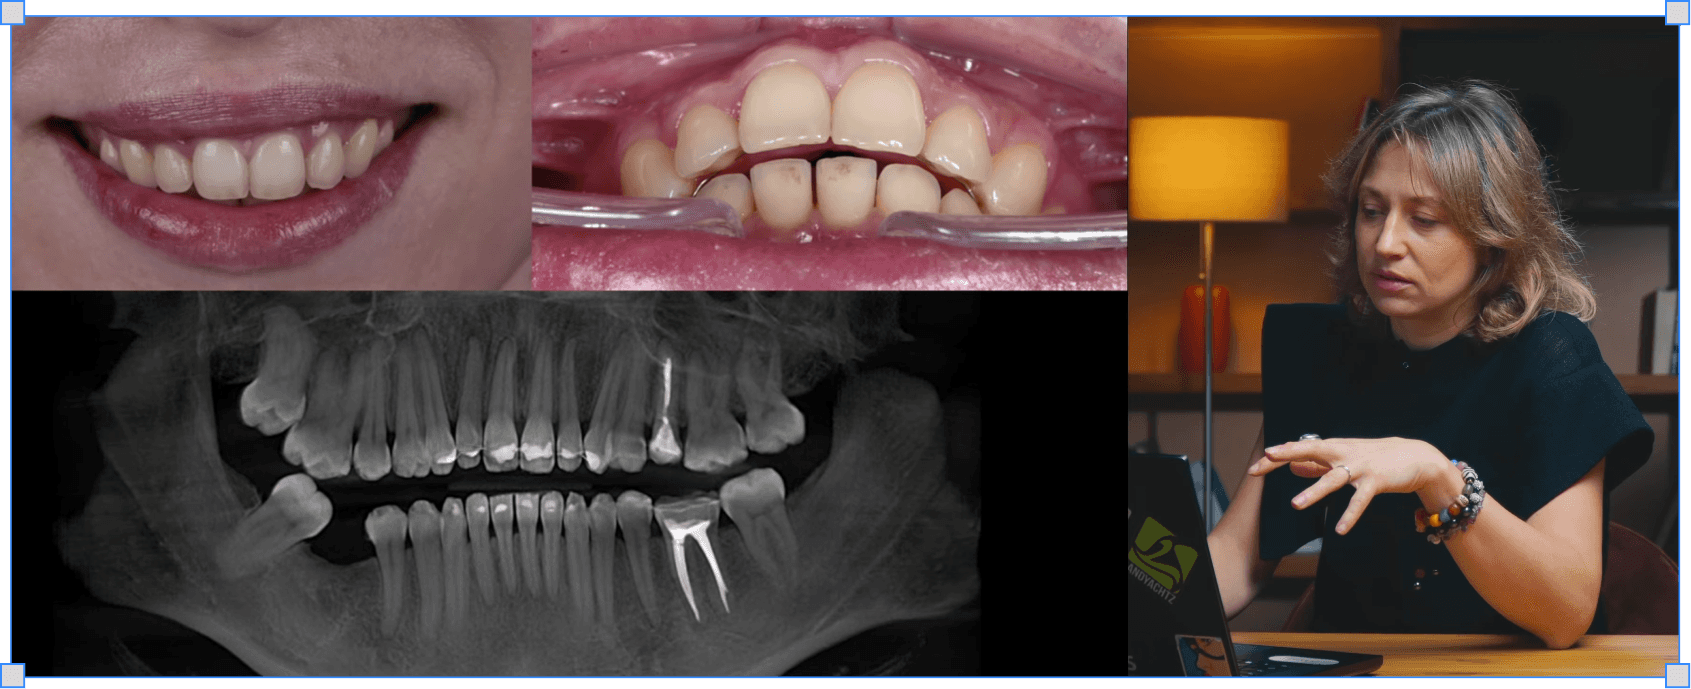

Клінічні кейси: